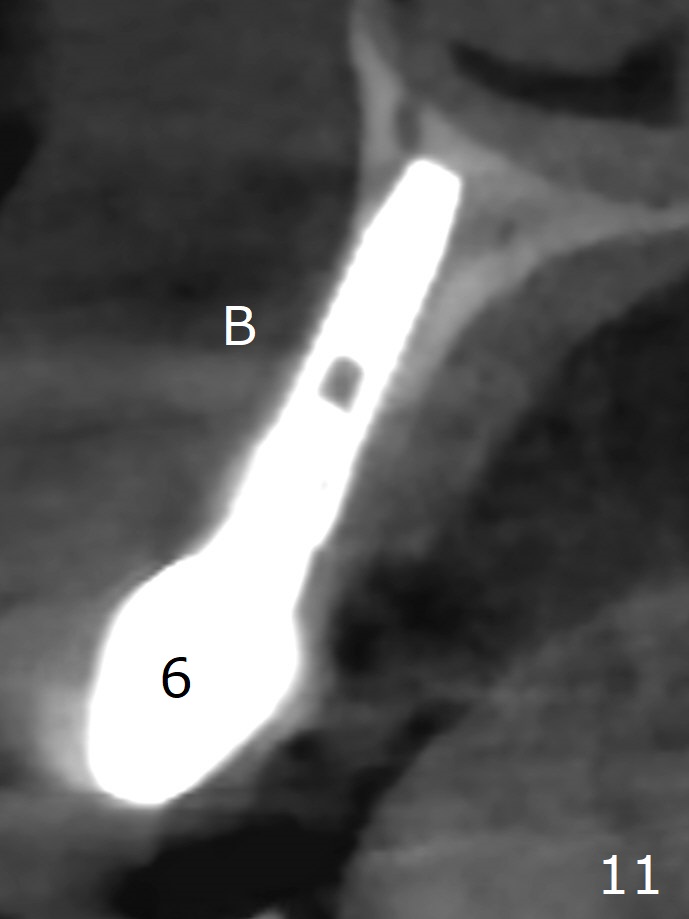

When the tooth #6 with loose crown and post (Fig.1) is extracted, there is no granulation tissue in the socket with the thin intact buccal plate. As planned, osteotomy is initiated in the mesio-palatal slope of the socket (Fig.2 red dashed line). After osteotomy for 3x20 mm (gingival level), a 3.8x15 mm dummy implant is placed partially (Fig.3 D). A final implant with the same dimension is placed with > 50 Ncm (Fig.4). Before and after placement of a 4.5x5(3) mm abutment, Vera graft is placed in the remaining socket space (mainly buccal, Fig.5 *). As routine, an immediate provisional is fabricated with occlusal clearance. The gingiva looks healthy around the provisional 1 week postop (Fig.6 P). Adjust and polish the mesioocclusal composite at #5 if necessary before impression. The bone graft appears to remain in place 4.5 months postop (Fig.7). A bevel buccal subgingival margin is placed prior to impression. The bone density around the coronal portion of the implant increases 9 months postop (4 months post cementation, Fig.8). There is no gingival erythema or edema around the implant crown at #6 ten months post cementation (Fig.6, as compared to preop condition and that of the neighboring crown (*)). Both the buccal and palatal plates are thin or absent 1 year 5 months post cementation (Fig.10,11, as compared to Fig.12 for the tooth #11 (thin buccal bone)). Socket shield should be done with a smaller implant.